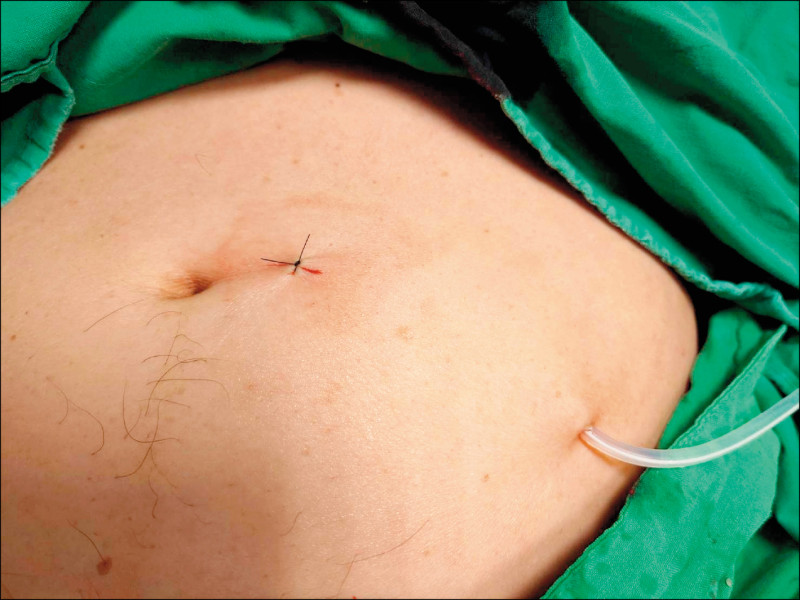

經與腎臟科醫師討論後,建議採用「腹膜透析導管」(Tenckhoff Catheter;又稱「Tenckhoff氏導管」)植入,以取代傳統腹水治療方式,作法是先在下腹部切開1個0.4公分左右的切口,再將導管的一端通過切口放進腹腔內,另一端則是橫向穿過皮下再伸出體外,之後以特殊環帶固定,全程使用局部麻醉可在門診進行,時間約20分鐘左右。

原本黃小姐一開始還擔心導管會外露,但實際上,只要用腰帶束住、衣服蓋起來,導管就不會被發現,隱密性極佳,且操作過程簡單,絲毫沒有不適的感覺。